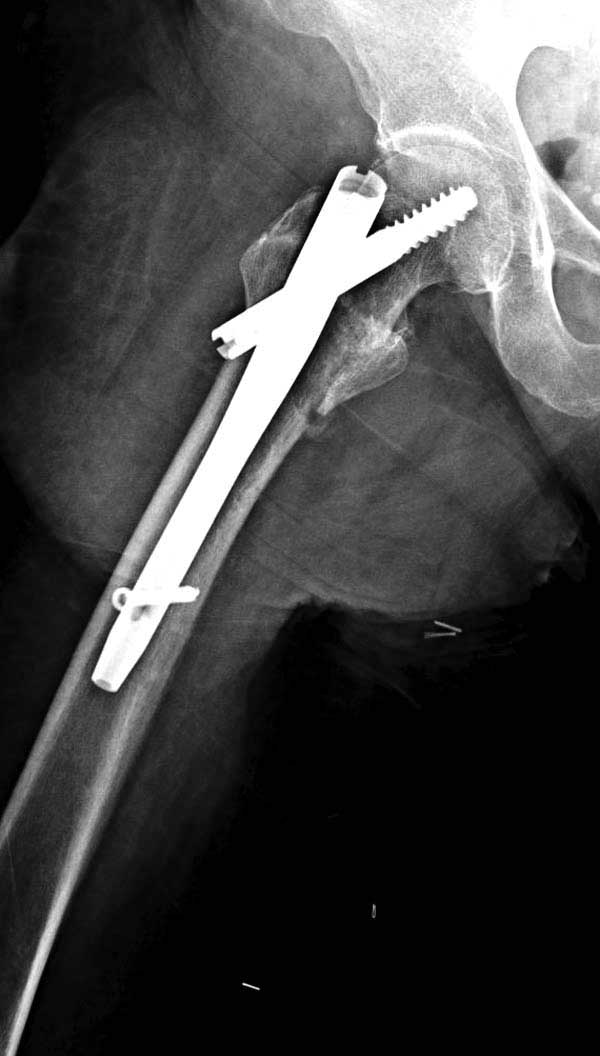

Банальный рутинный перелом чрезвертельной зоны лечимый DHS.

А по картинке можно сказать, что вроде бы все и неплохо. Предупредить миграцию шеечного винта при наружной ротации диафиза во время ходьбы достигают введением последнего поближе к переднему кортексу шейки. На Вашей картинке винт "смотрит" кзади. Отсутствие дополнительной боковой опоры для винта создает предпосылки для несостоятельности фиксации. (См. статью в прикреплении). Поэтому с ранней активизацией пациента в данном случае я бы подождал.

А пациент-то какой из себя?

При таком переломе мы бы тоже поставили вертельный гвоздь - на следующий день встать и побежать - чем не перспектива? На прямом снимке винт стоит замечательно, а коварный аксиальный подкачал, хотелось бы больше по центру шейки и головки завести. Да и смещение, какое-никакое, но есть. Посему - нагрузка 15 кг, а расширяли бы не раньше, чем через 5 недель.

Что касается данного перелома, то по-моему DHS или гамма - принципиальной разницы здесь конкретно нет - медиальная опора сохранена, при правильном исполнении можно ногу нагружать. Технически здесь выполнено на 3+, но если так же винт гаммы поставить - лучше не было бы.

Прилагаю снимок сделанный еще в стационаре через 2 недели после операции.

Первые снимки показывают технические погрешности установки DHS. Не была достигнута репозиция, конечность в флексии и шейка в ротации. Сегодня все меньше обращают внимание на параметры для оценки репозиции (S контуры Lowell в обеих проекциях и Garden Alignment Index, в норме 155 и 180 градусов), хотя такие простые тесты помогли бы дорепонировать смещение. Винт находится сзади в головке, что при нагрузке поменяет вектор и вместо компрессии в линии перелома срежет головку-Cut Out!

В зависимости от дистанции линии перелома и латерального кортекса надо использовать разной длины barrel, т.е. конец баррели не должен доходить до пределов перелома. Здесь конец длинного ствола упирается в медиальный фрагмент, что мешает созданию компрессии, а более короткий barrel создал бы запас для компрессии. В боковой пластине вместо 4х можно было ограничится двумя шурупами, потому что головка шурупа в 4.5 мм выдерживает давление до 350 кг.